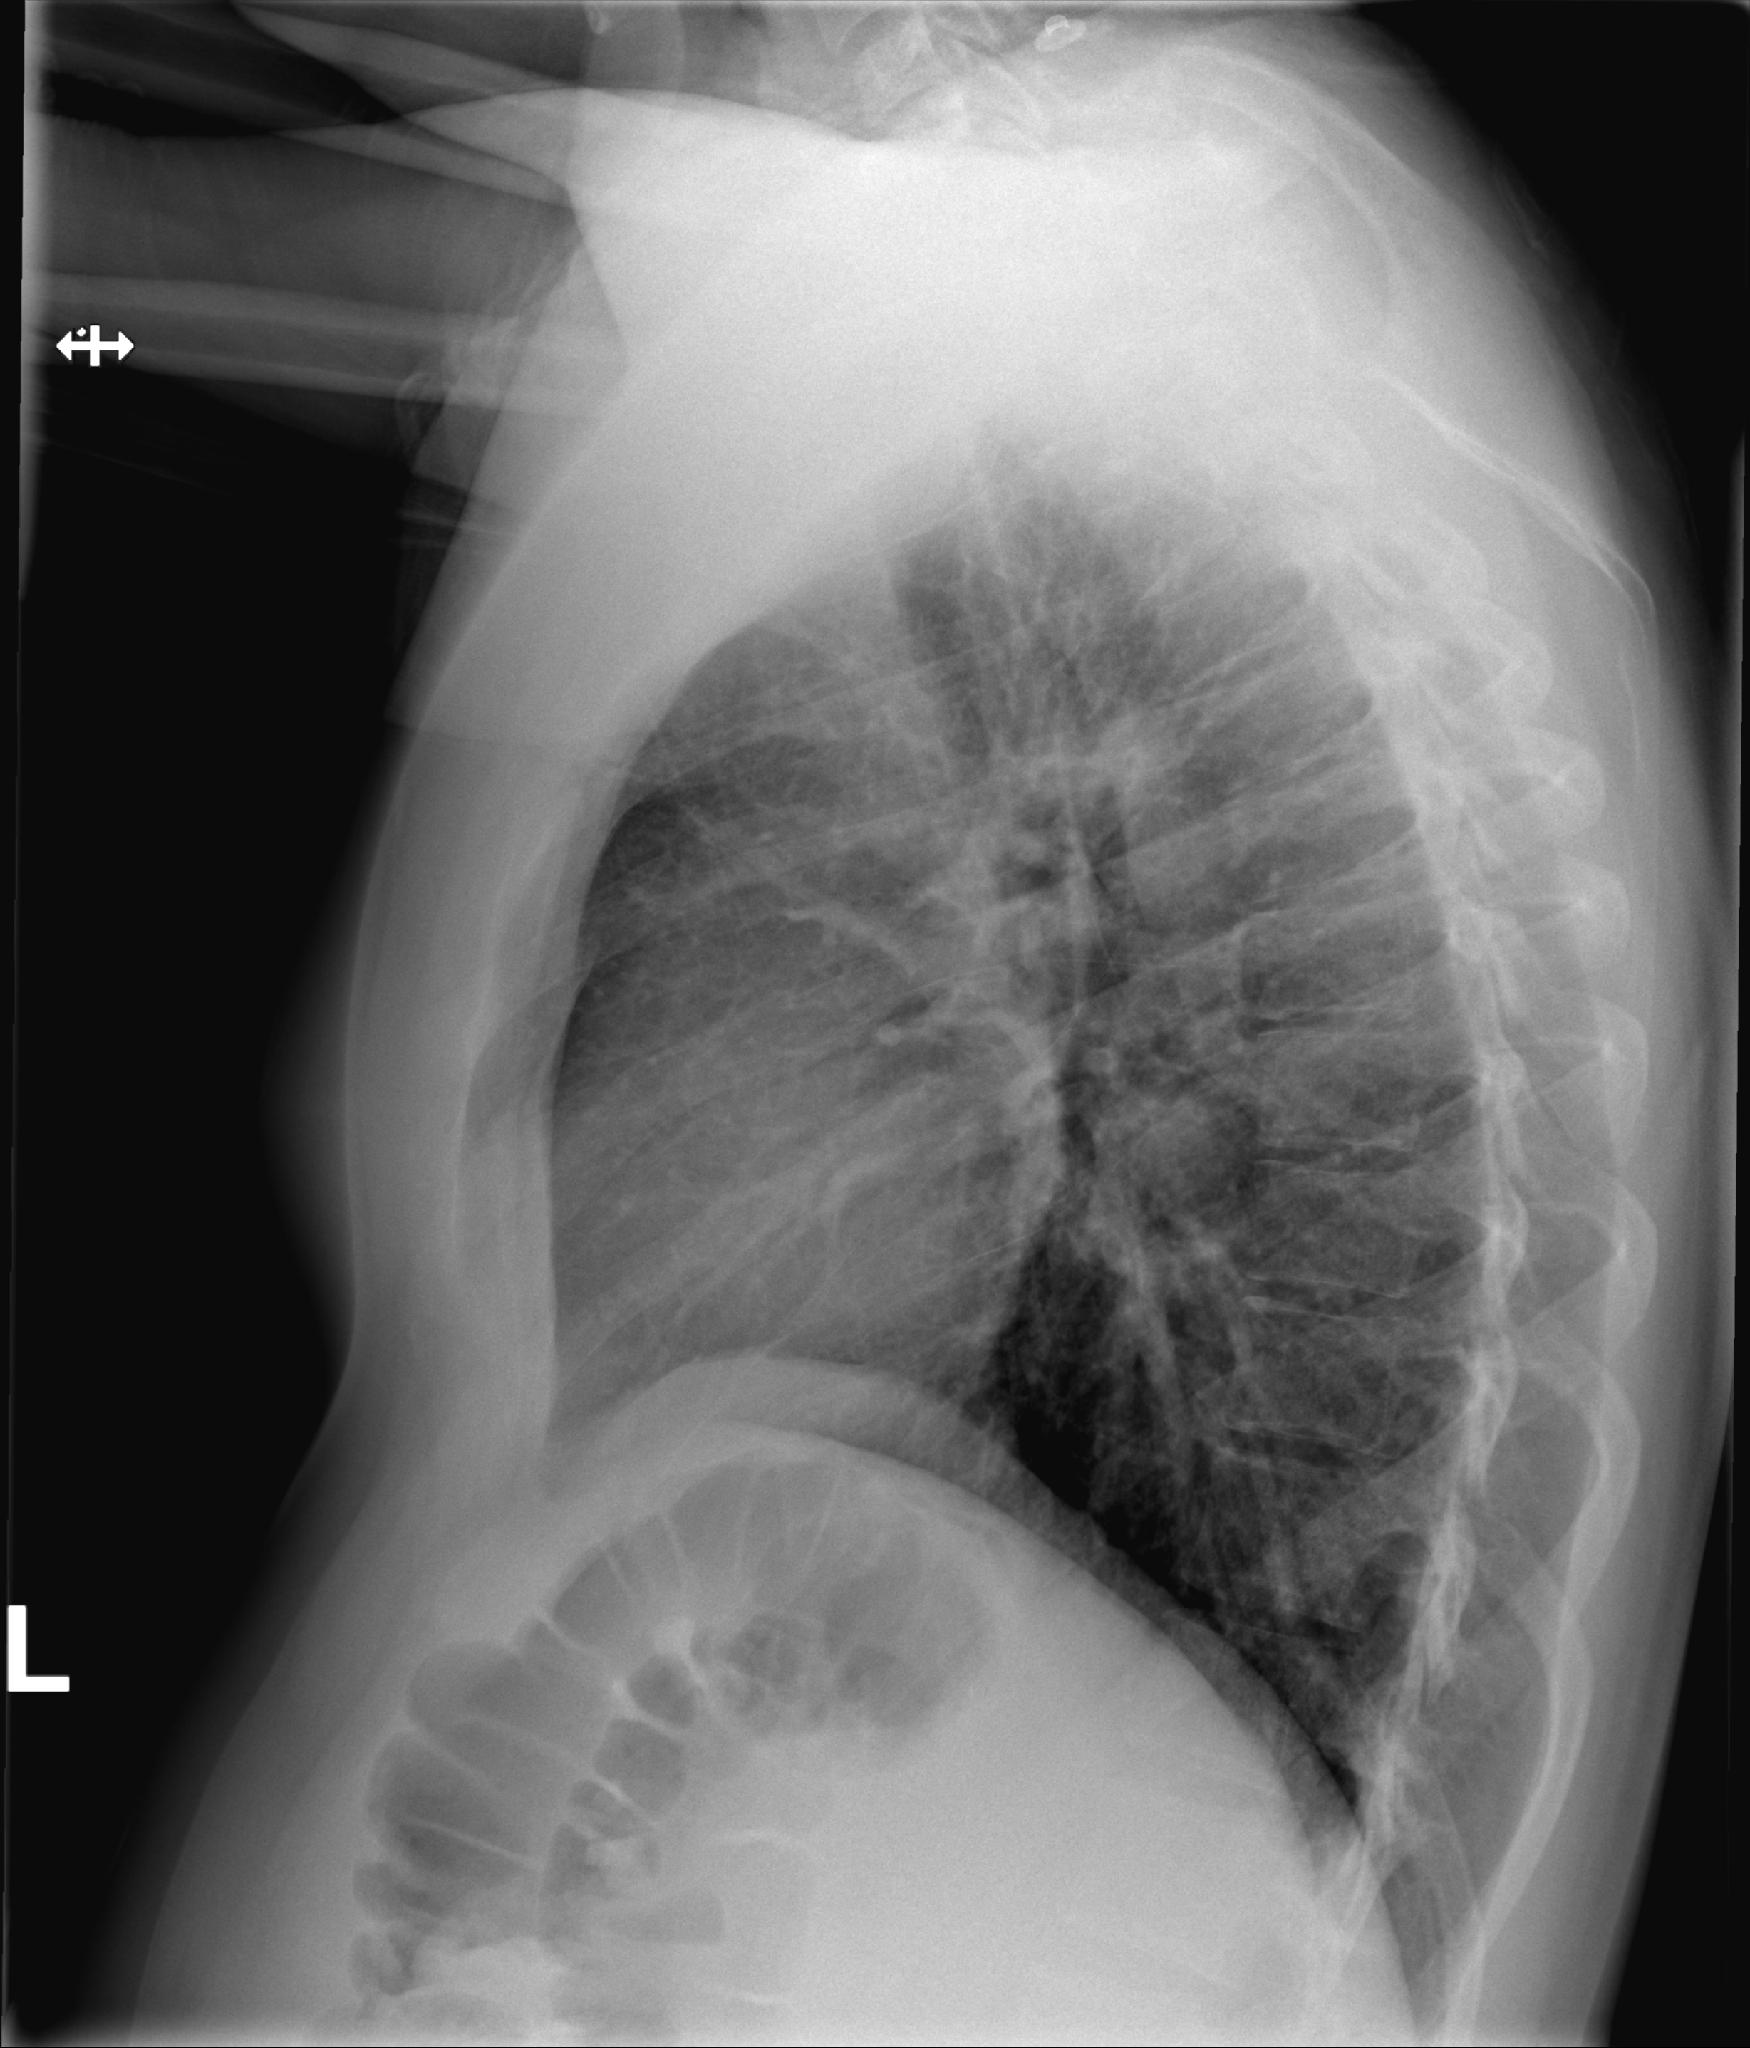

Scherp afgrensbaar diafragmakoepel. Heldere sinus pleura. Slank mediastinum superior. Hili opgebouwd uit bronchovasculaire structuren. Corfiguur binnen de norm. Longvaattekening binnen de norm. Geen circumscripte consolidaties. Echter matig afgrensbaar rechter harthelft. Afgebeeld bovenbuik zonder bijzonderheden. Skelet zonder relevante nevenbevindingen. Conclusie: Geen circumscripte consolidaties. Echter matig afgrensbaar rechter harthelft, beginnende consolidatie middenkwab niet uit te sluiten.

Bert heeft wel gelijk. Voor nu kan ik zeggen dat de foto dus als normaal wordt afgegeven met als enige bijzonderheid dat de rechter zijde van het hart niet scherp is te zien. Daar ligt de middelste van de 3 rechter  longkwabben tegen aan en misschien zit daar een kleine ontsteking. Het kan ook zijn dat er niks aan de hand is. Het mooist  zou zijn als er eerder al eens een foto is gemaakt om te vergelijken. Maar bespreek  het dus met je arts.

Beste Luuk, bedankt voor je snelle reactie. ik heb helaas geen foto die eerder is gemaakt, wel heb ik een foto van de zijkant die de zelfde tijd is gemaakt.